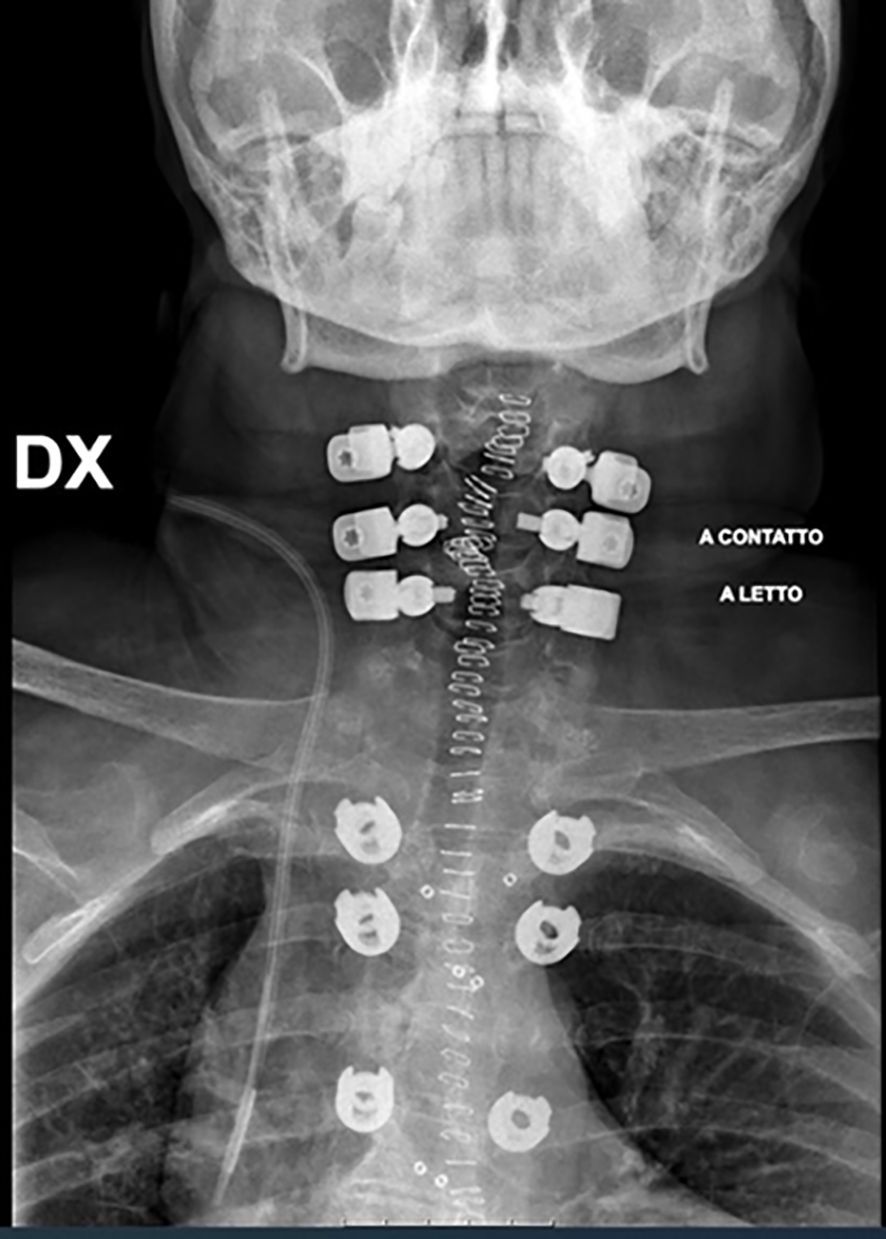

A hybrid system of carbon fiber rods, custom-made titanium connectors and cervical screws was used in the cervical and cervico-thoracic spine. CF-PEEK or LCFRP rods were used to bridge the cervical and thoracic spinal instrumentation. In cases where LCFRP rods were utilized, 5.5 mm titanium implants were placed in the thoracic spine, while in cases where CF-PEEK implants were utilized, 5.5 mm CF-PEEK screws were used instead. A customized titanium connector was used to connect the cervical/occipital fixation to the carbon rod. This customized titanium connector consists of a tulip for connection to the carbon fiber rod, and a stem for connection to the cervical/occipital fixation (Figures 1, 2). The connector stem could be bent and then cut or shortened as needed once the construct was secured (Figures 3, 4). The connections between the custom titanium connectors and the carbon fiber rods/standard screw tulips were secured using locking screws. The interface between the carbon fiber rod and the tulip of the custom titanium connector is illustrated by Figure 2, where the rod was press-fit into the connector tulip and retained in place by friction and interference. During final implantation, locking screws were also inserted into the tulips to further secure the connection between the tulips and the carbon fiber rods (Figure 3). A surgical drain was inserted, after which standard closure in layers was performed.

Nine (82%) patients underwent cervicothoracic posterior instrumentation, one (9%), occipito-cervico-thoracic instrumentation, and one (9%), occipito-cervical fixation. Mean construct length was 9(range 7-11) levels; mean number of non-instrumented levels was 3(range 2-5). LCFRP rods were used in 9/11(82%) cases and CF-PEEK rods, in 2/11(18%) cases. Anterior reconstruction was performed with non-vascularized iliac crest graft in 2/11(18%) cases.

This may also be in part due to the fact that we have sought to optimize the intraoperative placement of the screws, connectors, and rods. In the thoracic spine, the titanium screws were placed caudal to the level of the tumor to minimize interference of the implants with radiotherapy and imaging. In the cervical spine, lateral mass screws and the custom titanium connectors were placed cranial to the level of the pathology, and directed away from the tumor, so as to reduce potential implant interference. As far as possible, we have attempted to ensure that only the radiolucent carbon fiber rods remained at the level of the tumor (as illustrated by Figures 3 and 4), in order to facilitate postoperative imaging and radiotherapy delivery.